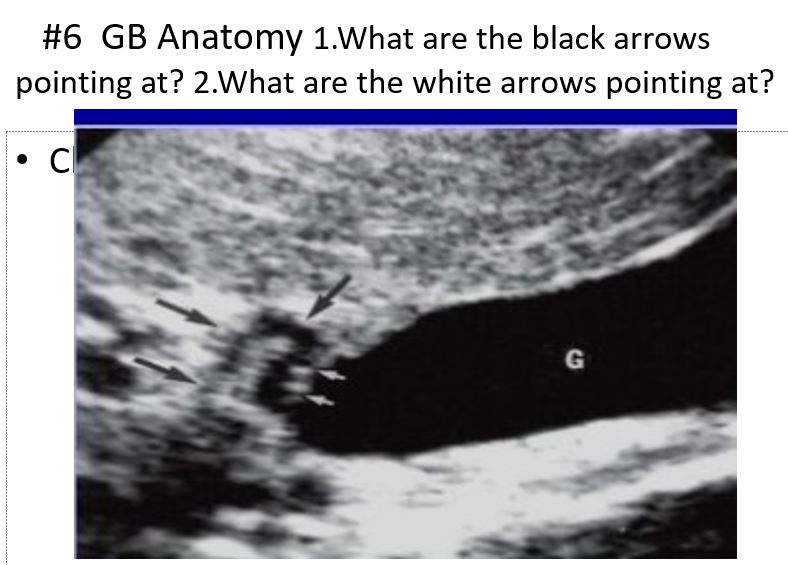

black: cystic duct

white: valves of heister